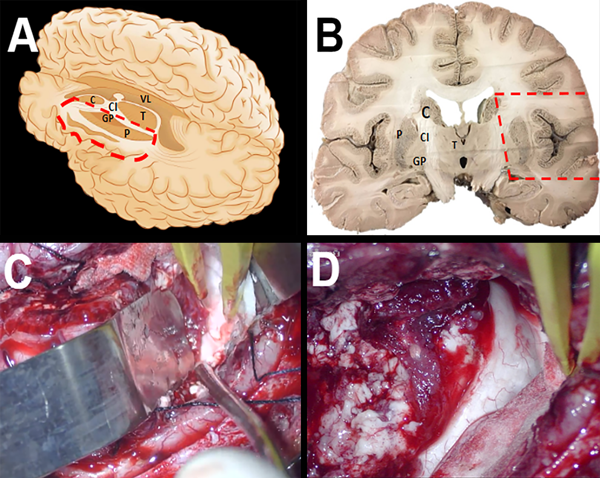

Figura 2. Dibujo representativo, disecciones e imágenes intraoperatorias que ilustran la técnica de HPI modificada. Después de entrar en el ventrículo, el opérculo frontal y temporal junto con la ínsula y porciones del núcleo caudado, el tálamo y los ganglios basales, se separan y extraen justo lateralmente al plexo coroideo(C). Esto expone el sistema ventricular (D).

Figura 3. Disecciones representativas e imágenes intraoperatorias que ilustran la técnica de hemisferotomía lateral modificada. (A-D). Desde dentro del ventrículo se incide el cuerpo calloso junto con las conexiones profundas de sustancia blanca entre la rodilla del cuerpo calloso y la corteza frontal orbitaria (A-D). Se desconecta la sustancia blanca adicional entre el cuerpo calloso posterior y el hipocampo posterior (E-F). Se realiza una amigdalohipocampectomía selectiva en la que se extirpa el uncus y la amígdala mediante aspiración subpial. Se retira el hipocampo anterior hasta alcanzar la fisura coroidea, sin dejar aferentes hipocampales.

Para describir de manera más detallada la HPI modificada, se practica una incisión cortical inicial, realizada a lo largo del opérculo frontal paralela al ventrículo y profundizada hasta que se ingresa al asta frontal del ventrículo lateral (Fig. 1 A-B). La apertura ventricular continúa posteriormente hasta el atrio del ventrículo lateral y se continúa posteriormente hasta la extensión anterior del asta temporal (Fig. 1 A-D). En este punto, se identifican, coagulan y ligan las ramas proximales de la arteria cerebral media, distales a los vasos perforantes profundos (Fig. 1 E-F). Usando el plexo coroideo como nuestro límite medial, el opérculo frontal y temporal junto con la ínsula y porciones del núcleo caudado, el tálamo y los ganglios basales se separan y resecan, exponiendo de esta manera el sistema ventricular (Fig. 2 A-D). Desde el asta frontal del ventrículo lateral, se realiza una callosotomía trans-ventricular, desconectando el cuerpo calloso hasta identificar la aracnoides sobre las arterias pericallosas (Fig. 3 A-D). Esta callosotomía transventricular se extiende luego desde el asta frontal hasta la desconexión occipital mesial. Posteriormente, una vez alrededor del esplenio, se extiende la incisión medial anteriormente hasta alcanzar la fisura coroidea, desconectando la fimbria del hipocampo del fórnix (Fig. 3 E-F). Se realiza una desconexión frontal profunda incidiendo justo por delante de los ganglios basales en un plano coronal desde el aspecto anterior del cuerpo calloso hasta la aracnoides de la región orbitofrontal. La identificación del giro recto y el tracto olfatorio proporciona buenos puntos de referencia anatómicos al llegar a la etapa más profunda. Preservar la piamadre basal agrega seguridad a este paso. Finalmente se realiza una amigdalo-hipocampectomía selectiva donde se extirpa el uncus y la amígdala mediante aspiración subpial y se reseca el hipocampo anterior hasta llegar a la fisura coroidea (Fig. 3 E-F).